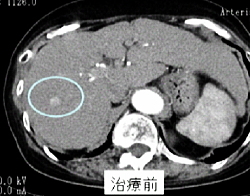

肝臓にできたがんを治療する方法の一つに動脈塞栓術があります。これは、がんに血液を送っている血管内に塞栓物質といわれるゼリー状の薬を注入して栄養の供給を絶ち、がん細胞を死滅させる方法です。通常は、その効果を高めるために抗がん剤を併せて注入します。動脈塞栓術を行うためには、薬を肝臓まで運ぶ細いプラスチックのチューブ(カテーテル)が必要です。カテーテルは、足の付け根の動脈に細い針を刺し、その穴を通して血管内に挿入します。針を刺す前には局所麻酔を行いますのでカテーテル挿入の痛みは注射程度の軽いものです。動脈は全身どこにでもつながっているためカテーテルは容易に肝臓の中まで入ってゆくことができます(図1)。

がんの個数が限られている場合は、カテーテルの中にさらにさらに細いカテーテル(マイクロカテーテル)を挿入し、一つ一つを選択的に治療することも可能ですが(図2)、この治療法はむしろ肝臓内に多数のがん病巣がある場合にその真価を発揮します。仮に100個をこえる病巣があったとしても、肝機能に余力があれば一度にすべての病巣を治療対象とすることもできます。しかし、手術やラジオ波焼しゃく療法(RFA)などの局所治療に比べると一回あたりの治療効果が劣るため、多くの場合は数週~数ヶ月の間隔をあけて繰り返し行う必要があります。